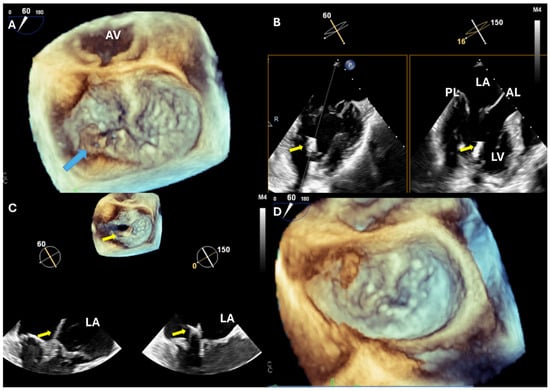

| MV repair | Describe MR mechanism Measure leaflet length Measure annulus size Estimate MR severity | Ensure sufficient MR reduction No flail part Exclude iatrogenic MV stenosis |